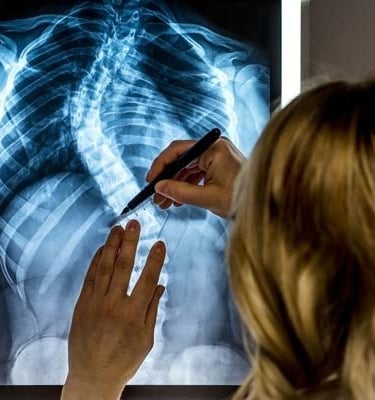

ويُؤخَذ تشخيص الجنف عادةً بعين الاعتبار عندما يتجاوز انحناء العمود الفقري حدًا معيّنًا في الفحوصات التصويرية، وغالبًا ما يتم قياس ذلك باستخدام زاوية كوب (Cobb angle) في صور الأشعة السينية.

يبدأ تشخيص الجنف بتقييم سريري يشمل أخذ تاريخ صحي مفصّل وفحصًا بدنيًا شاملًا. وقد يلاحظ الممارس الصحي وجود عدم تماثل في مستوى الكتفين أو الوركين أو الخصر، أو اختلافًا في وضعية الجسم. وتُستخدم الفحوصات التصويرية، مثل الأشعة السينية، لتأكيد وجود الانحناء وقياس درجة شدّته.